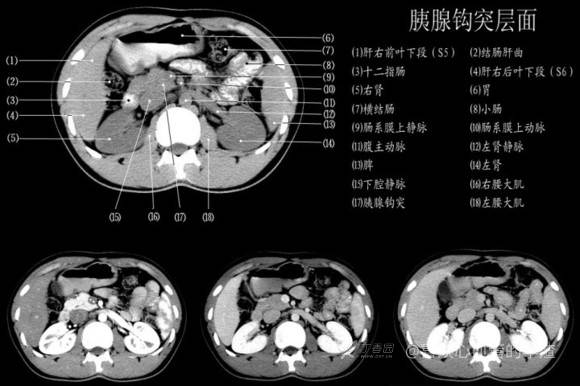

其实你离掌握上腹部 CT 影像只有一套高清实用图谱的距离,下面把我最喜欢的这本图谱分享给大家,为了方便阅读,我加了中文标识。后面附赠几张血管相对位置解剖关系图片,帮助大家理解(文中多图,建议在 wifi 环境下查看)。